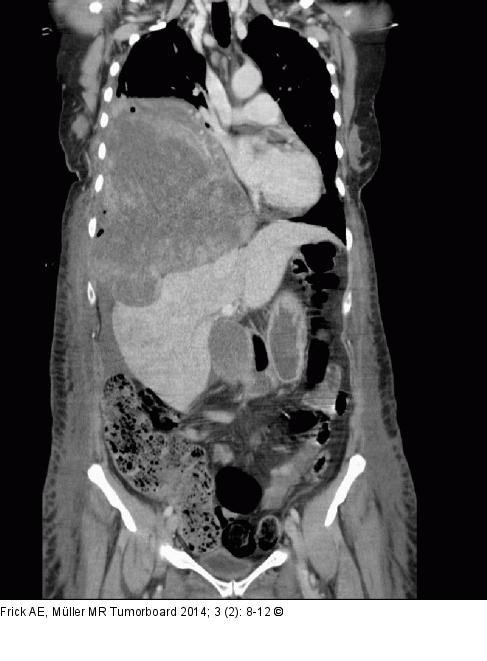

Abbildung 2: Biphasisches Synovialsarkom Koronare Rekonstruktion der CT mit Kontrastmittel: Deutliche Abgrenzbarkeit einer ausgedehnten rechtsthorakalen Raumforderung mit Mediastinalverlagerung nach links und Kompression des rechten Leberlappens. Der Tumor ist heterogen und scheint großteils Koagel bzw. ein Hämatom zu beinhalten. Tumorsuspekte kontrastmittelaufnehmende Anteile der Raumforderung liegen vor allem ventrobasal auf Höhe des 4. bis 7. Interkostalraumes vor. Eine Vorwölbung eines Tumoranteils mit Kompression der Leber ist sichtbar, aber es zeigt sich kein sicherer Hinweis auf eine Kapselinfiltration der Leber. Großteils vorhandene Fetttrennungslinie zum Perikard/Cor, wobei an den ventrobasalen Anteil auf Höhe des Perikardergusses eine eindeutige Abgrenzbarkeit nicht gegeben ist. Arrosion der 11. Rippe rechts dorsal. |